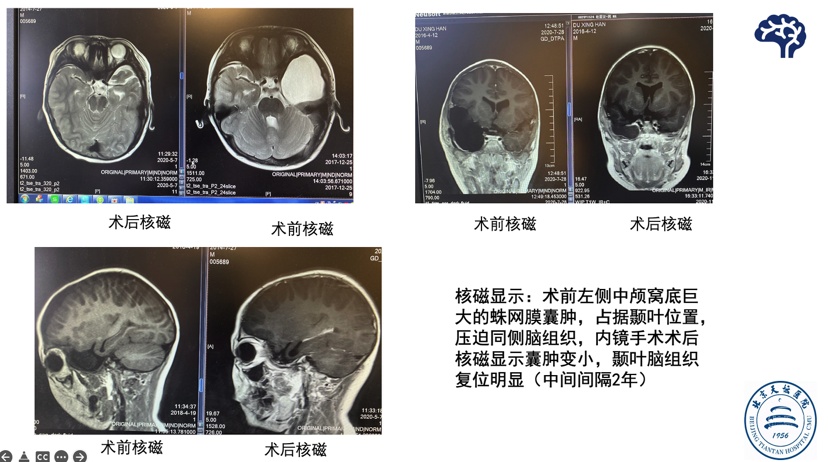

病例一 患儿男,4岁因蛛网膜囊肿行内镜下蛛网膜囊肿造瘘术(2018年),术后2年复查脑组织复位

病例二 患儿5岁,左侧外侧裂蛛网膜囊肿,以癫痫起病,内镜下造瘘后,癫痫好转